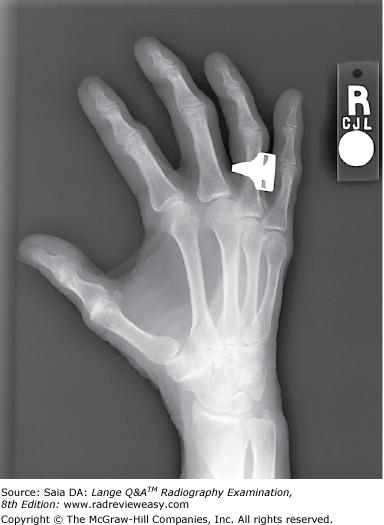

With which of the following does the trapezium articulate?

A Fifth metacarpal

B First metacarpal

C Distal radius

D Distal ulna

-The first metacarpal, on the lateral side of the hand, articulates with the most lateral carpal of the distal carpal row, the greater multangular/trapezium. This articulation forms a rather unique and very versatile saddle joint named for the shape of its articulating surfaces.